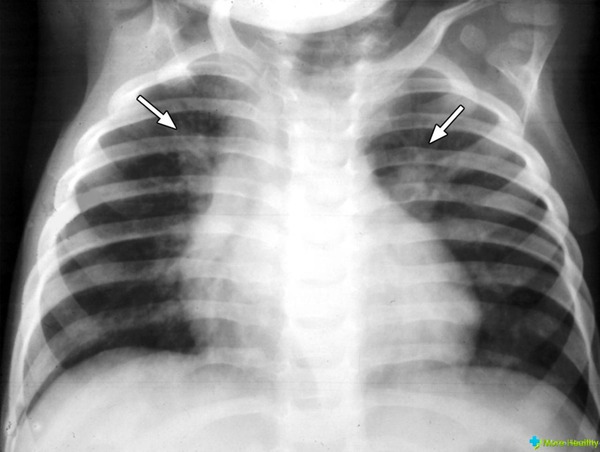

Не каждый случай пневмонии, вызванной бактериальной инфекцией, является клебсиеллезом, однако каждое поражение легких клебсиеллезом у детей и взрослых характеризуется особенно серьезным течением.

Признаки схожи с признаками любой другой бактериальной пневмонии:

- внезапное начало заболевания;

- повышенная температура тела — обычно достигает 39°C, но может быть еще выше;

- чувство холода;

- интенсивный кашель;

- обильное густое кровянисто-слизистое отделение.

Клебсиелла представляет особую опасность для ткани альвеол. Поражение этой бактерией может вызвать развитие гнойных процессов, которые могут привести к некрозу тканей. Патологические изменения в альвеолах при клебсиеллезе часто приводят к частичной или полной ателектазии легких.